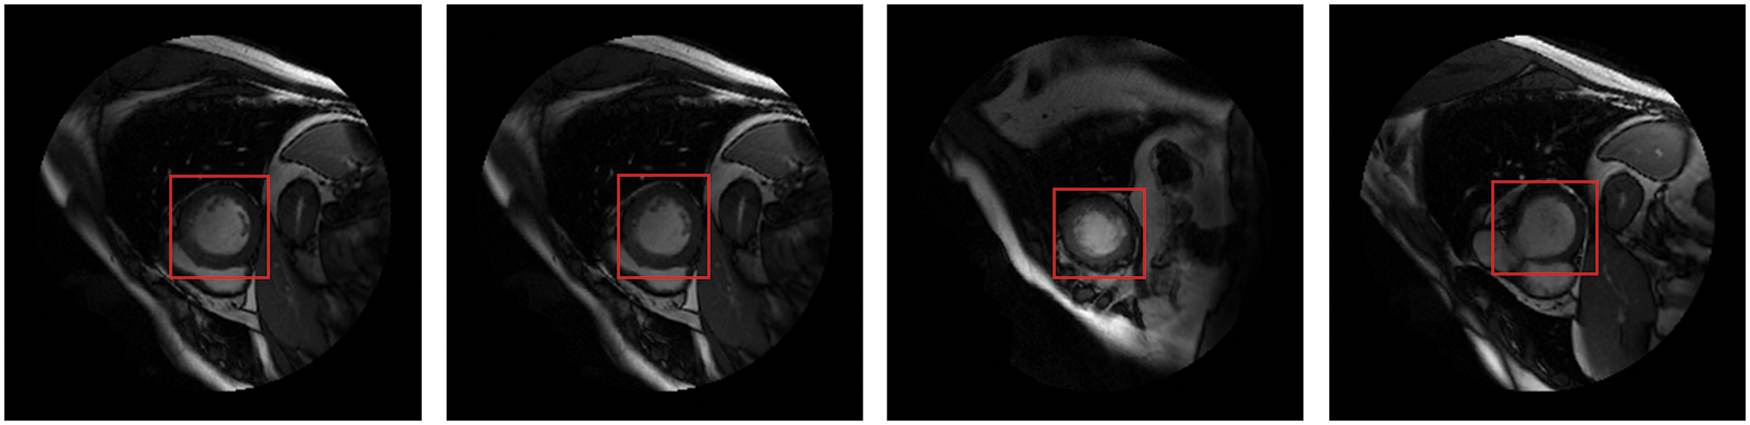

Detecting anatomical organs has been receiving increased attention in medical image analysis because it only extracts ROI from the background. Recently, short-axis MRI images have played an essential role in the evaluation of cardiac functions [1,2] to diagnose cardiovascular diseases such as myocardial infarction (MI) [3]. Cardiac MRI images consist of the LV and right ventricle, surrounded by other organs such as the lungs and diaphragm. Thus, LV localization is extremely useful in reducing computational load, particularly for deep learning algorithms. The fundamental advantage of LV localization is that it improves the effectiveness of subsequent techniques like regression [4] and segmentation [5–7] by extracting only the LV area and ignoring the other organs, as illustrated in Fig. 1.

Figure 1: The LV localization from cardiac short-axis MRI images at various shapes and sizes